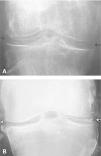

Artritis por microcristales (2). Enfermedad por depósito de cristales de pirofosfato cálcico. Otras artritis por microcristales